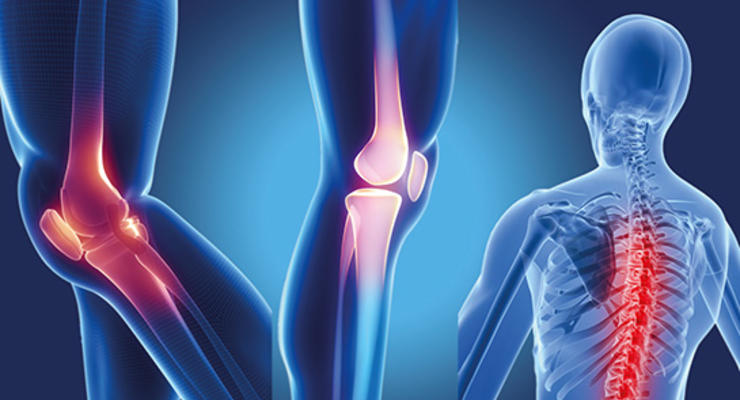

Eklem ağrılarının başlıca nedeni nedir?

Ortopedi ve Travmatoloji Anabilim Dalı Uzmanı Yrd. Doç. Dr. Deniz Aydın halk arasında kireçlenme olarak bilinen, eklem kıkırdak hasarları ve tedavi yöntemleri hakkında açıklamalarda bulundu.

Ciddi eklem ağrılarının nedeni olan ve halk arasında kireçlenme olarak bilinen hastalığın başta diz olmak üzere birçok büyük eklemi etkileyebildiğini söyleyen Yakın Doğu Üniversitesi Hastanesi Ortopedi ve Travmatoloji Anabilim Dalı Uzmanı Yrd. Doç. Dr. Deniz Aydın, kireçlenmenin eklem kıkırdağının yıkılması, kıkırdak altındaki kemikte sertleşme, kist oluşması, eklem çevresinde yeni kemik oluşumlarının ve eklemin çevresindeki yumuşak dokularda ödem gelişmesi ile ortaya çıkan bir hastalık olduğunu söyledi. Kireçlenmeyle ortaya çıkan şikayetlere de açıklamalarında yer veren Yrd. Doç. Dr. Deniz Aydın, tutulan ekleme göre değişik klinik sorunlar oluşabilse de başlıca şikayetlerin eklem hareketlerinde kısıtlanma, hareket ederken artan ağrı, eklemde şekil bozukluğu gelişmesi ve tekrarlayan şişlikler olarak karşımıza çıktığını söyledi.